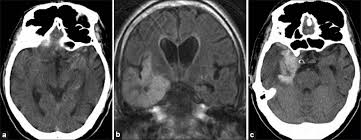

A 40‑year‑old male patient with herpes simplex virus encephalitis presented with altered sensorium. The differential diagnoses include limbic encephalitis (paraneoplastic), gliomatosis cerebri, and status epilepticus. Herpes simplex (hsv) encephalitis is the most common cause of fatal sporadic fulminant necrotizing viral encephalitis and has characteristic imaging findings. Severe edema, petechial hemorrhage, and massive hemorrhagic tissue necrosis can be seen on gross specimens. Two subtypes are recognized which differ in demographics, virus, and pattern of involvement.

Watershed distribution ischemia in areas remote from the primary herpetic lesions may be seen. Herpes simplex encephalitis typically manifests in older adults (about 50% of cases) with headache, fever, altered sensorium, and even seizure. Hippocampus, temporal lobe, and the ponsfigure 4a.7. Herpes simplex virus (hsv) is the most common cause of acute fatal sporadic encephalitis, with a particular predilection for the limbic system. Unfortunately, the imaging findings are often nonspecific with overlapping appearances. This lesion was seen in all patients as the disease progressed. Severe edema, petechial hemorrhage, and massive hemorrhagic tissue necrosis can be seen on gross specimens. He was managed with intravenous acyclovir 30mg/kg and supportive therapy. that appeared in a recent issue of clinical infectious diseases. However, mimics of hse, including other infections and increasingly recognized autoimmune causes, have been described in cases of tl encephalitis. But changes are not specific for hsv (e.g. The characteristic feature of hse is hemorrhagic necrosis of the temporal lobe. The basal ganglia are usually spared.

We describe the spectrum of etiologies associated with temporal lobe (tl) encephalitis and identify clinical and radiologic features that distinguish herpes simplex encephalitis (hse) from its mimics. In addition, it was observed in various pathological conditions: A feasibility study of quantifying longitudinal brain changes in herpes simplex virus (hsv) encephalitis using magnetic resonance imaging (mri) and stereology. Encephalitis, magnetic resonance imaging, meningoencephalitis, viral. In the present study, flair bth was most frequently seen in patients with hsv encephalitis. that appeared in a recent issue of clinical infectious diseases. 1 mri t2 weighted image, showing bilateral temporal lobe hyperintensities. A brain biopsy was performed and the histology was consistent with encephalitis.